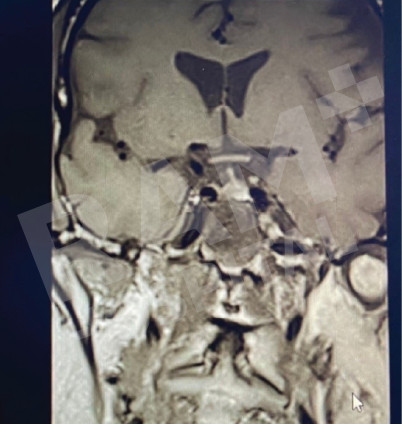

磁共振成像(MRI)可清晰、细致地显示垂体的异常病变,精准定位垂体腺瘤的位置;结合静脉造影增强检查,还能明确腺瘤的具体位置与病变性质,同时清晰呈现脑部周边组织及鼻窦的情况。这一项检查结果可为制定诊疗方案、随访评估垂体腺瘤的治疗效果,乃至规划手术方案提供明确、可靠的依据。

| 术前 | 术后 |